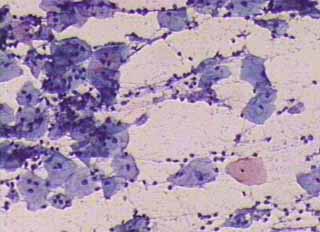

Πινακοθήκη κυτταρολογικών ευρημάτων ΙΙΙ

Οι πινακοθήκες κυτταρολογικών ευρημάτων, έχουν σαν στόχο να εμπλουτίσουν την κυτταρολογική εμπειρία σπουδαστών και ειδικευομένων, όπως ένας άτλαντας.

Παρουησιάζονται λοιπόν τυχαία ευρήματα, από το καθημερινό γυναικολογικό ιατρείο.